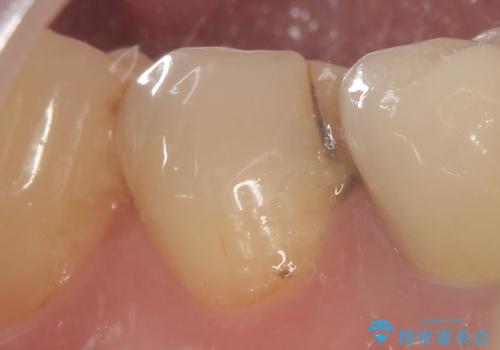

古い詰め物とう蝕を除去し、審美的で適合が良く二次う蝕になりにくいセラミックインレーによる修復を行いました。

審美的な仕上がりと自然な咬み心地に喜んで下さいました。

インレーの種類:セラミックインレー(e-max press)